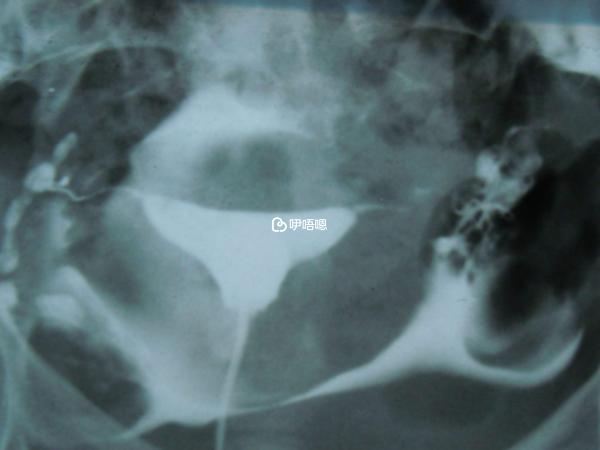

後來醫生說我老公活力低是支原體引起的讓我老公吃抗生素治療,我想著肯定要對症下藥才能好的快,就給他開了兩盒抗生素,但是當時我也懷疑我輸卵管有問題,反正老公當時吃了抗生素不能備孕,我乾脆也造影看看輸卵管算了,來了月經就預約,做完結果是兩側通而欠暢。